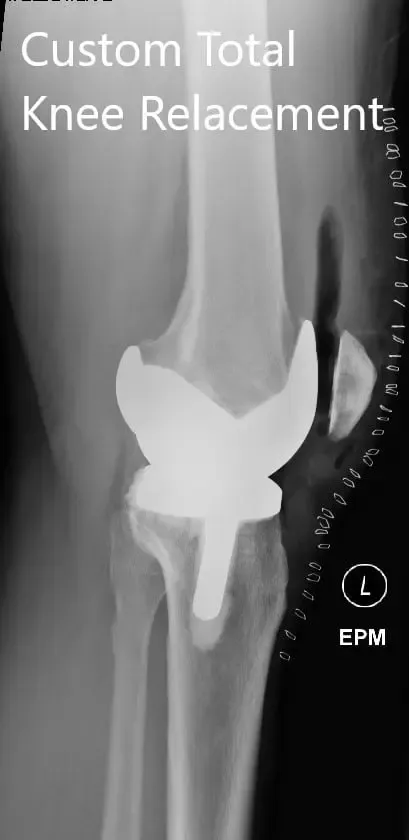

Postoperative X-ray showing the lateral view of the right and the left knee